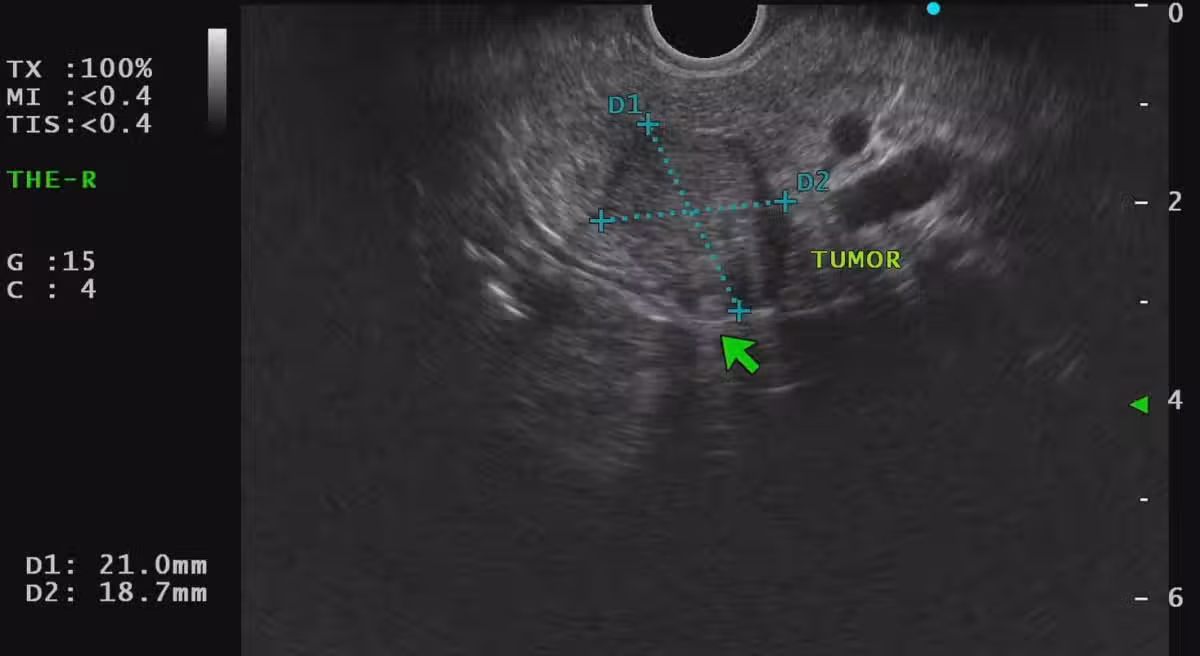

圖片來源:胰臟醫師林相宏

林相宏醫師表示「胰臟神經內分泌瘤」是比較少見的胰臟癌類型,目前產生原因不明,部分與遺傳基因異常有關,近年來還有上升趨勢,它的生長速度較慢,存活率也比「胰臟腺癌」高,不過因為初期通常沒有明顯症狀,所以通常都是晚期,或是已有轉移現象才會被發現。醫師表示:「這個病患成功在還沒有轉移前,手術切除根治,而胰臟篩檢的價值就是如此」。